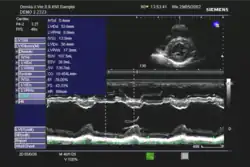

Die Ejektionsfraktion kann mit verschiedenen Untersuchungsverfahren gemessen werden, in absteigender Häufigkeit:

- Echokardiographie

In der klinischen Praxis erfolgt die Abschätzung der Ejektionsfraktion häufig nach dem visuellen Eindruck; dies wird bei subjektiv normaler Pumpfunktion als ausreichend angesehen. Bei eingeschränkter Pumpfunktion sollte eine quantitative Bestimmung mit Hilfe der Scheibchensummationsmethode nach Simpson erfolgen;[3] die Quantifizierung mittels M-Mode nach Teichholz wird als zu ungenau angesehen.[3][4]